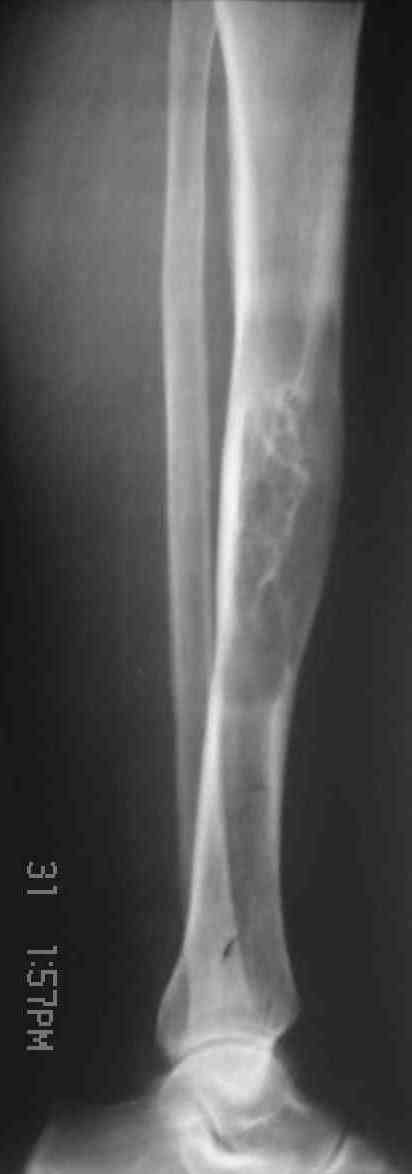

Здравствуйте, уважаемые коллеги. Женщина 62 лет с гигантоклеточной? опухолью диафиза большеберцовой кости.

В анамнезе хроническая травматизация. Заметила месяца три назад, не болит. Кожа над образованием не изменена. Рентгенограммы прилагаются. Наша военно-научная мысль бьется в направлении резекции кости в пределах здоровых тканей,фиксации блокированным стержнем с последующим выращиванием костного регенерата. Или лучше выполнить краеву резекцию, эксколхеацию и пластику дефекта (предварительно верифицировав диагноз при помощи трепан-биопсии)? Есть некоторые сомнения, что это действительно ОБК. Хотелось бы ваше мнение. Алексей.